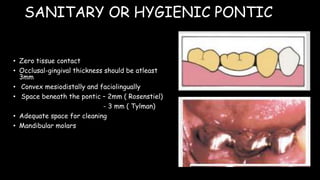

The document discusses pontic design for fixed dental prostheses. It covers pretreatment assessment of residual ridge contours, classifications of ridge deformities, surgical modification techniques, and ideal requirements for pontics. Pontic designs are classified based on their shape and materials. Factors in pontic selection include esthetics and oral hygiene. Common designs for anterior and posterior regions are described, including sanitary, ovate, and saddle pontics. Biological considerations for pontic design involve maintaining the residual ridge, abutment teeth, and supporting tissues.